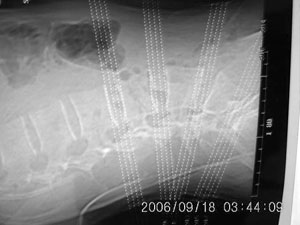

以下是引用守望可可西里在2006-9-18 21:29:00的发言:[br][br] 马尾肿瘤,密度较低,大部分似乎呈囊性变(看着很费眼),考虑室管膜瘤,建议mri。

以下是引用dyg在2006-9-18 22:27:00的发言:[br]正常脊髓.[br]分析:人的脊髓从枕大孔开始至腰1.2椎体为止,有2个生理膨大,分为颈膨大和腰膨大;该病人脊髓须然从腰段开始直至马尾似乎膨大,胆是与上段脊髓密度没有多大变化,所以我认为是正常膨大之延续;当然最好做ct增强或mri检查,排除肿瘤.

以下是引用飞虎在2006-9-18 20:18:00的发言:[br]部分椎管内密度不均且无ct值 故mri检查